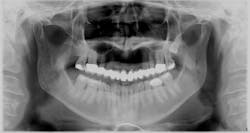

Pre-operative panoramic radiograph

Next came the comprehensive evaluation by the dentist, which was just as extensive. Her existing bridge from Nos. 3 to 14 had fractured porcelain, recurrent decay on No. 4 mesial, No. 5 distal, No. 12 distal, No. 13 mesial and distal, and No. 14 mesial. Additionally, decay was noted on No. 18 buccal and No. 20 distocclusal.